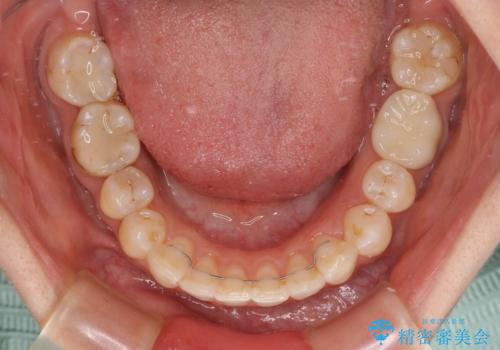

- 下顎の前歯が隠れていることと、デコボコを気にして来院された患者様です。

銀歯やムシ歯処置の必要な歯が奥歯にあり気になっていたので、矯正治療の途中でセラミッククラウンへ変更し、その後歯列を仕上げていくこととしました。

咬み合わせと目立っていた銀歯が改善され、患者様には大変満足していただきました。